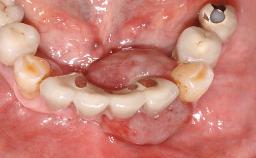

Surgical treatment of a 67-year-old male patient exhibiting an extended edentulous space in the anterior maxilla after the removal of three hopeless incisor teeth.

The case concludes with the presentation of the final prosthesis and the esthetic outcome, demonstrating stable soft tissue conditions and stable bone crest levels at the 3-year follow-up.